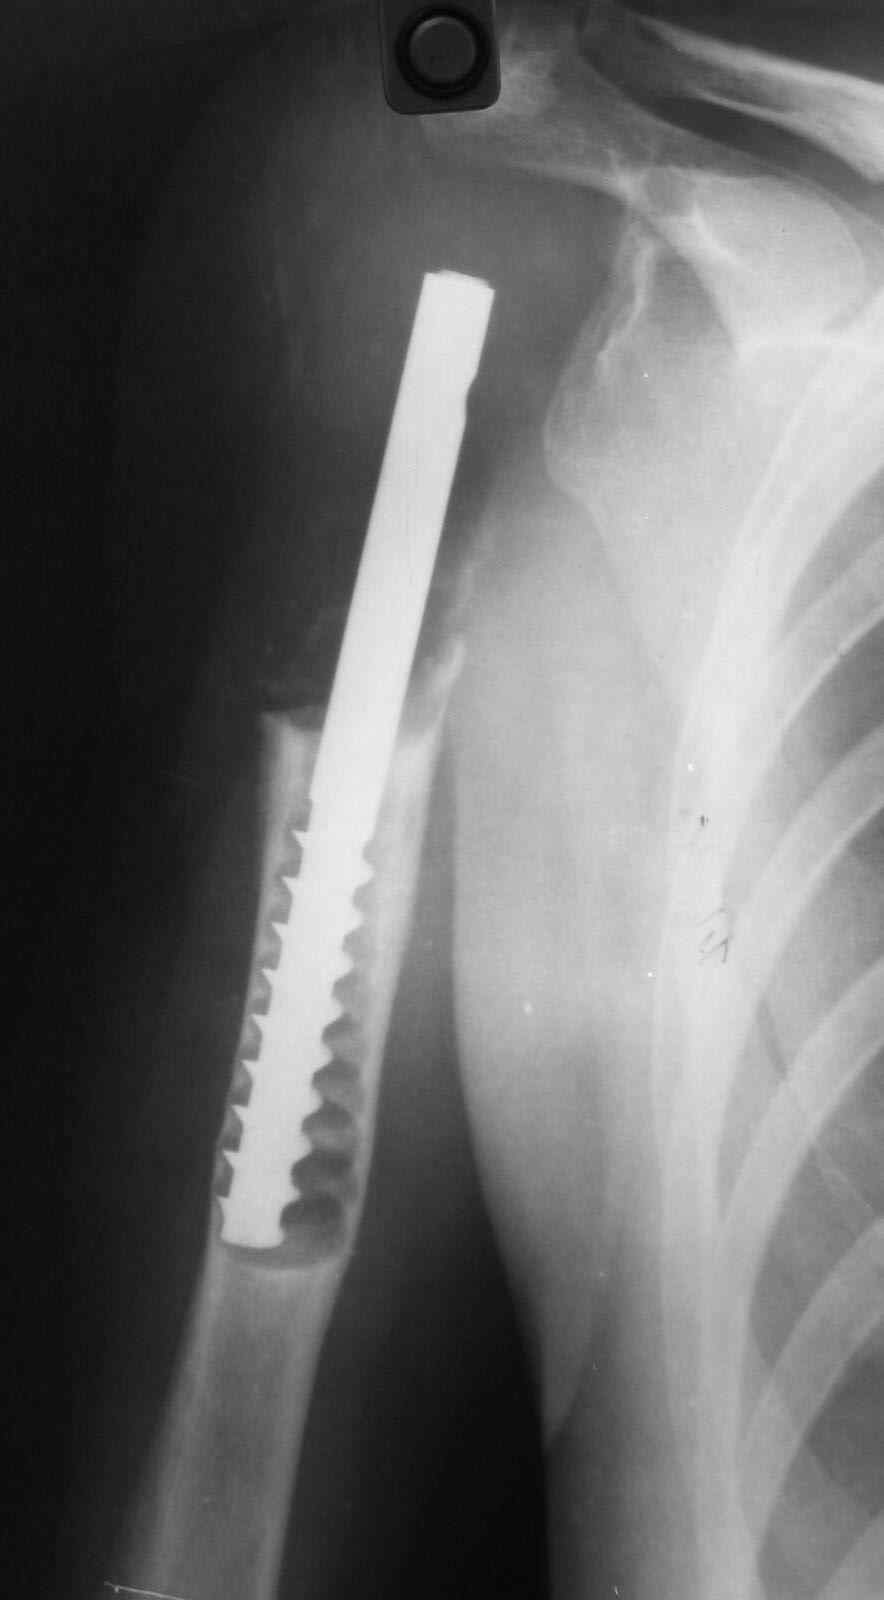

Больная 34 года операрована 14 лет назад по поводу литической формы ОБК головки плечвой кости

14 лет назад больной имлапнтирован протез плечевой кости выполненый по методике Воронцова на штифте-штопоре Сиваша,за 2 года до имлапнатации в онкологическом учереждении больной выполнена резекция проксимальоной части плечевой кости по поводу ОБК, ксенотрансплантации головки, и последующем его удалением на фоне гнойного процесса. У больной имелся втянутый обширный рубец и болтающееся плечо, афункциональная верхняя конечность, выраженный косметический дефект.П/опрационный период без осложнений, сохранялась выраженная контрактура в плечевом суставе, но стаилизация плеча и косметический эффект больную устраивал,даллее контакт с больной был утерян ( поменяла место жителсьтва. Через 14 лет полноценной жизни сельской жешщины ,больная нашла нас с клиникой выраженной нестабильности протеза. Категорически отказалась от замены протеза.

Выполнена операция- малоинвазивно проведена LCP пластина в образованный канал над головкой протеза, фиксирована к протезу и дистально к плечевой кости, на зоной резорбции трепонирована кость, удалена соединительно-тканная оболочка, полость заполнена chronOS. П/о период без осложнений, клиника нестабильность купирована.Прошло 2 года по телефону сообщила, что у нее все хорошо, продолжает жить счастливой жизнью сельской труженицы

Головка отлита из акрилоксида( то чем мы располагали в прошлом веке), он полность Р-прозрачен, по методике Воронцова рекомендовалось добавлять Р-контрастные добавки,например сульфат бария, учитывая, что он давал раковины в полимере, мы это не сделали.Кстати, довольно крепкий получился, затупили 2 сверла.